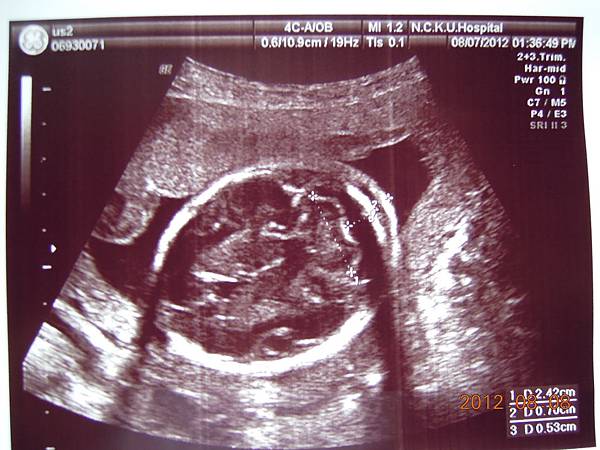

可以看到的是在逼逼的上方剛好被胎盤擋著,比較看不到他的正面,除了肛門無法看到(怕沒有肛門),醫師說現在看不到,小雞雞也沒照他的大小(我怕他發育不良),其他身體器官包括腦部剖有量測他的大小及羊水多寡(我怕像上次一樣羊水太少),今天量出來是12,喔彌陀佛~~

這是他給我的報告,都是一些代號,游醫師說明很快,不過我聽他說沒問題,就比較放心,裡面有把每個器官大約生長到幾週做個說明,大致都在22~24周,逼逼體重約697g~